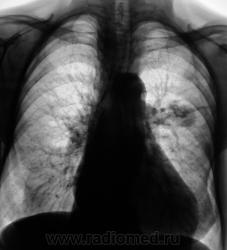

А клиника какова? ПО снимкам можно предположить и новообразование (как мне кажется наиболее вероятно) и туберкулому S6

Помоему образование, тяжистость ну очень интересная.

Неоднородность, очень плотное... гамартрохондрома, тератома, а-v-аневризма... Мне недостаточно для диагностики

Здравствуйте, уважаемый Валентин Львович! Склоняюсь к мысли периферического новообразования. На томограммах хорошо виден патогномоничный симптом "тень на веревочке". Ну и остальное. Неровные, нечеткие контуры, неоднородная структура. Зло!

Ну, мы так и сделали, выставили "периферический". Пациент уже в областном ОД.

В ООД был прооперирован, но дальнейшей судьбы не знаю.